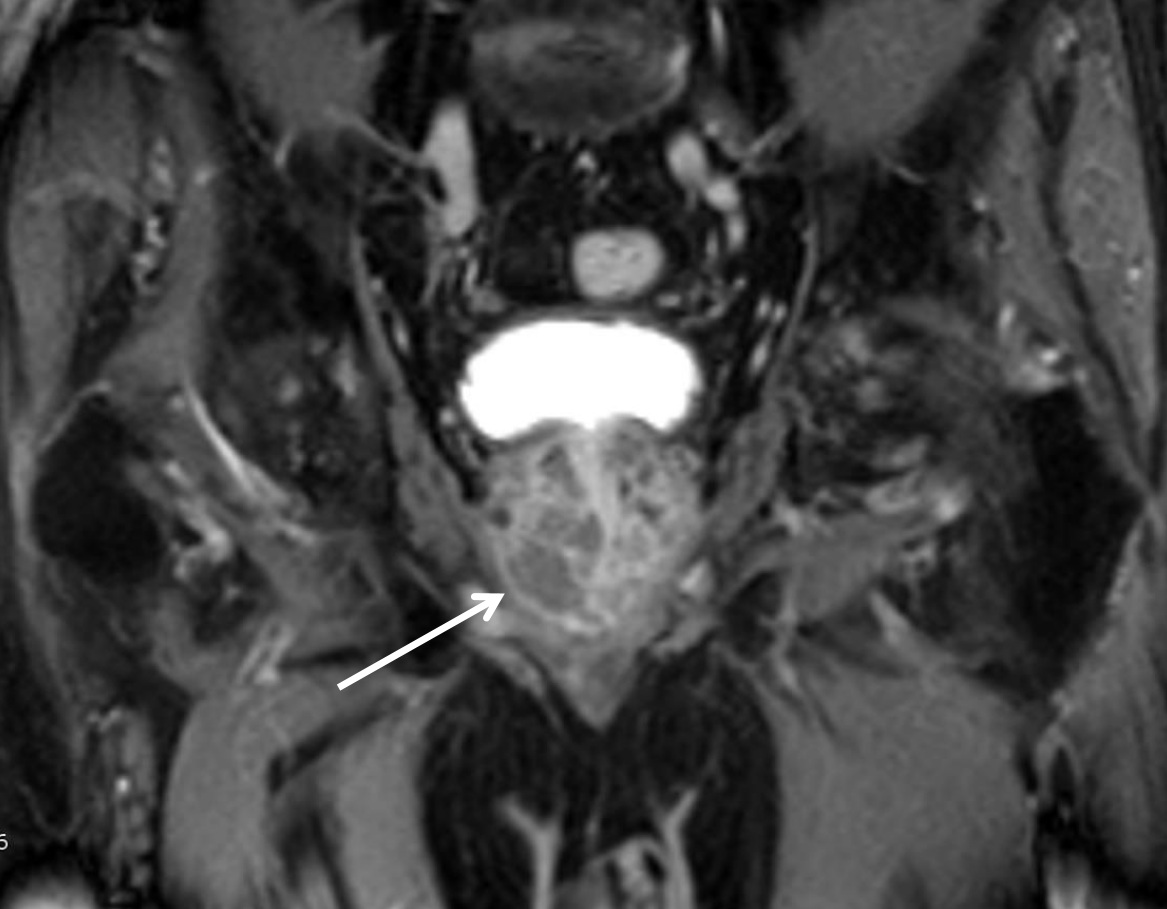

КТ-исследование абсцесса малого таза: Визуализация и диагностика